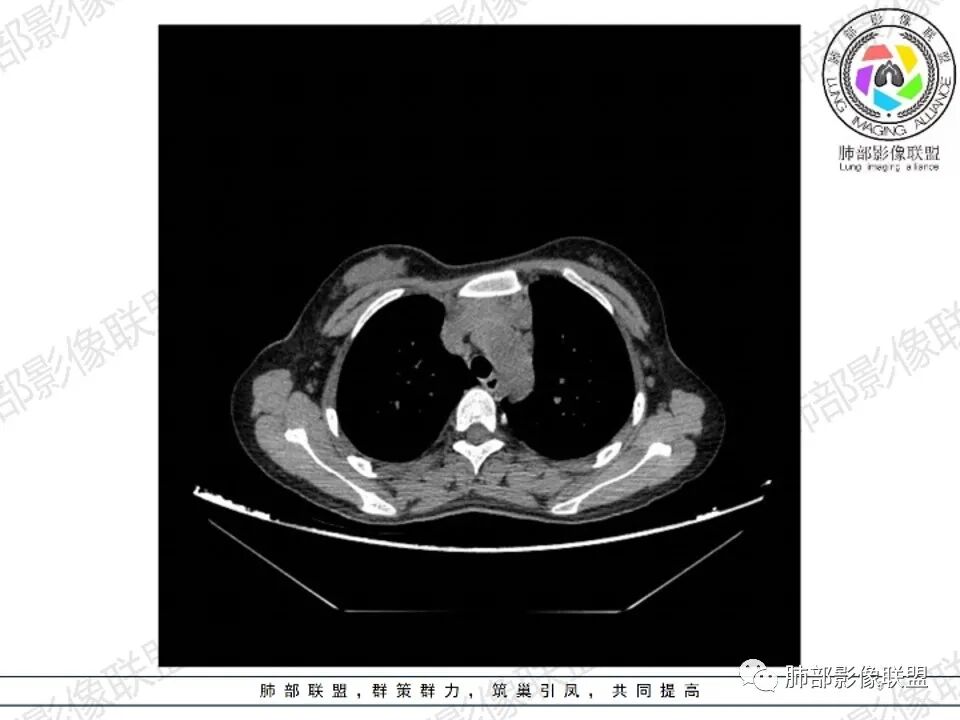

2.影像显示前纵隔不规则块状影,依势贴附心脏大血管旁,密度不均,边界不甚清楚,有结节融合感。

3.病灶轻度不均匀强化,可见血管穿行,散在液性低密度区。

双肺门未见肿大淋巴结。

4.双侧腋窝区见增大淋巴结,边界清楚。